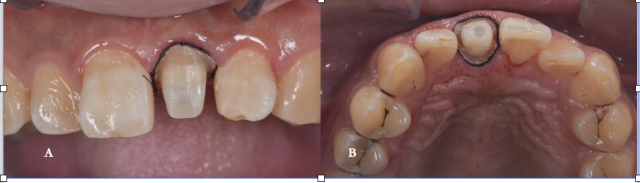

牙体预备排龈 A.唇面观;B.?面观

A.树脂核堆塑;B.牙体预备;C.根尖保留4mm根充物植入纤维桩的术后影像;D.两中切牙近远中比例检测;E.11去龋;F.11树脂充填,11、22邻面去釉抛光